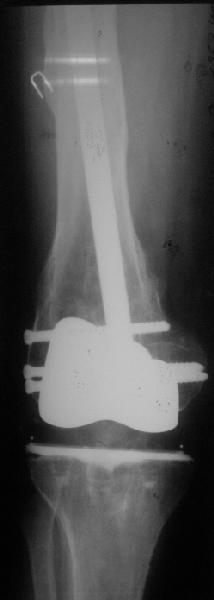

Добрый день! В нашу больничку поступил пациент после бытовой травмы - упал, подвернув ногу. На RG-граммах перелом дистального метаэпифиза бедренной кости. Пациент спутанно рассказывает, где и как он лечился раньше.10 лет назад - коррегирующая остеотомия по поводу деформирующего артроза коленного сустава, 3 года назад в 1 градской больнице г. Москвы выполнено эндопротезирование коленного сустава,площадка большеберцовой кости, со слов пациента, деформировалась около года назад (на фоне остеопороза). Сейчас получил травму в результате падения с высоты собственного роста.Что посоветуете?

Видимо, самое "модное" на сегодня - малоинвазивный остеосинтез пластиной с угловой стабильностью. Распространенный вариант и закрытый интромедуллярный остеосинтез ретроградно. Хотя у нас было бы сделано антеградно - лешево и сердито, действительно малоинвазивно, в сустав не надо влезать. Нет риска прорезания порозной кости с миграцией в сустав, что возможно при ретроградном - гвоздь вводится через вырез в бедреннм компоненте, туда же может и вывалиться. А антеградный - упрется в протез. Как раз вчера заходил больной через полтора года после такой операции. Снимки в приложении.